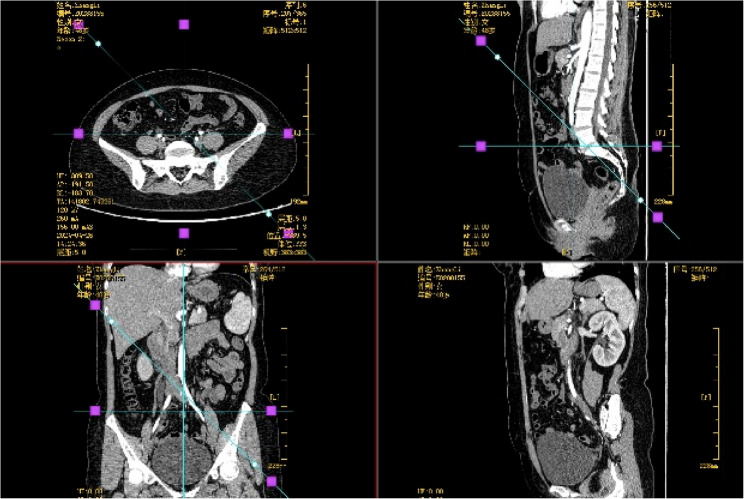

Results: The patient underwent laparoscopic total hysterectomy and bilateral salpingectomy at our hospital more than one year prior because of adenomyosis. No pharmacological treatment was provided postsurgery. One year later, the patient presented with right lumbar discomfort. Imaging revealed hydronephrosis of the right kidney and dilation of the right ureter, leading to a diagnosis of right ureteral endometriosis. Laparoscopic excision of the ureteral endometriotic lesion was performed. Pathology confirmed right ureteral endometriosis with glandular cystic expansion. Postsurgery, the patient was treated with gonadotropin-releasing hormone agonist (GnRH-a) therapy (3.6 mg of goserelin via subcutaneous injection every 28 days for a total of six cycles). Treatment is ongoing. Follow-up ultrasound revealed no abnormalities in the kidneys or ureters, and no recurrence was observed during the five months of follow-up.